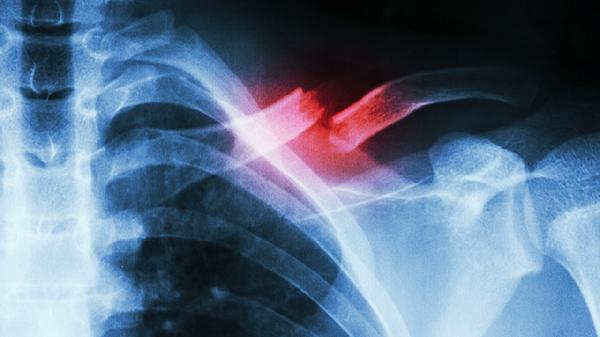

肋骨骨折一般可遵医嘱使用布洛芬缓释胶囊、对乙酰氨基酚片、塞来昔布胶囊、阿司匹林肠溶片、氨酚双氢可待因片等药物缓解疼痛。肋骨骨折多由外伤导致,表现为局部疼痛、肿胀、活动受限等症状,需及时就医明确骨折程度,避免自行用药延误治疗。